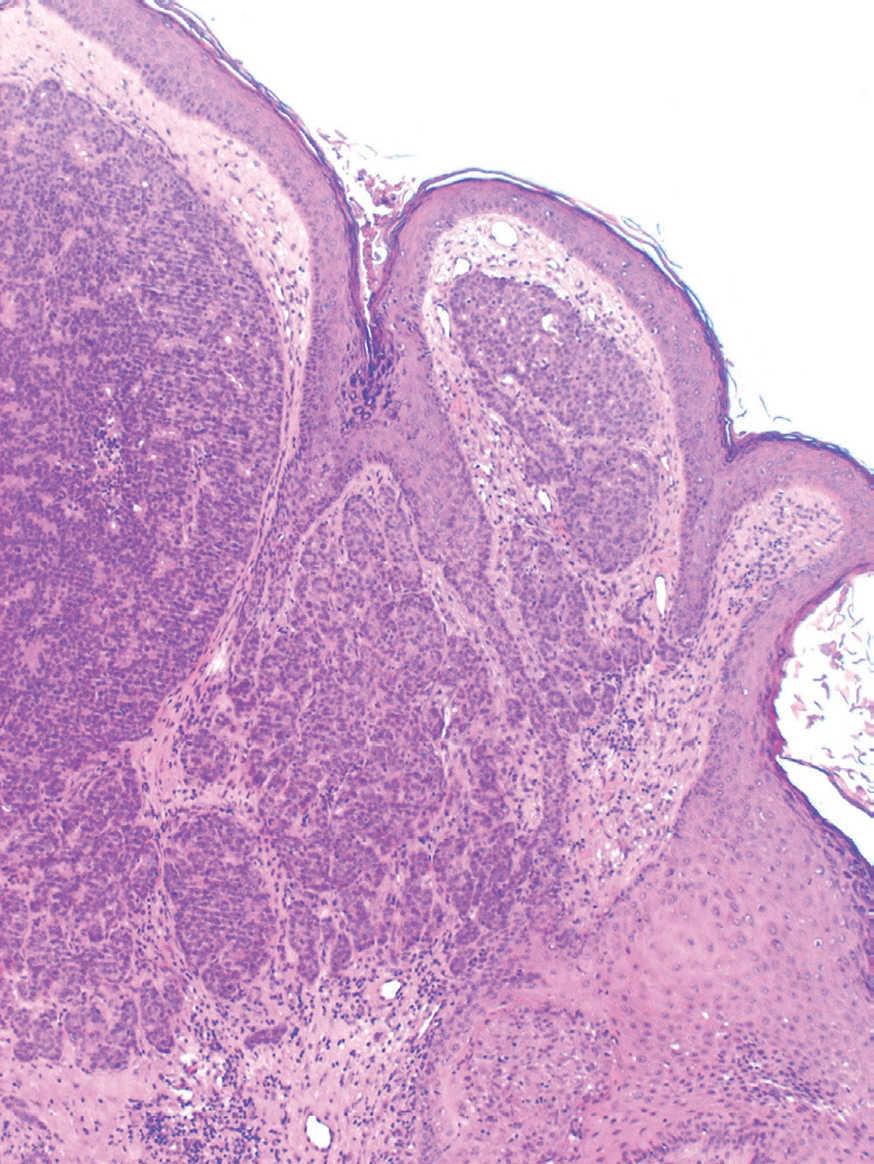

Se realizó una biopsia cuyo estudio histopatológico evidenció un tumor epitelial sólido con luces glandulares intratumorales en la dermis profunda, compatible con un carcinoma ductal infiltrante de mama (fig. 2).

Fig. 2.--Tumor epitelial sólido con un aspecto multinodular en la dermis. (Hematoxilina-eosina, x40.)